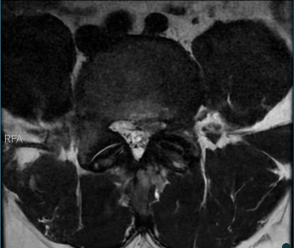

Após medidas conservadoras para melhora do quadro, que não houve resposta ao tratamento, paciente foi hospitalizado para manejo da dor. Durante a hospitalização, foi realizado um exame de ressonância magnética (RM), que mostrou alterações degenerativas do segmento lombar da coluna vertebral, destacando-se: abaulamento discal difuso em nível L4-L5, com componente protruso subarticular à esquerda, que toca a raiz descendente homolateral, edema entre os processos espinhosos de L2-L3, L3-L4 e L5-S1, por provável sobrecarga mecânica. Assim, considerando os resultados dos exames de imagem, bem como o quadro clínico do paciente e a refratariedade ao tratamento conservador, o departamento de neurocirurgia afirmou que seria necessário um procedimento cirúrgico para resolução da condição apresentada.

Figura 1. RM da coluna lombar (sequência T2 ponderada, plano sagital) evidenciando alteração na morfologia e no sinal do disco intervertebral em nível L4-L5, com redução da altura discal e protrusão posterior, com compressão do saco dural. Observa-se também hipersinal em T2 no espaço epidural posterior, compatível com alterações inflamatórias pós-operatórias.